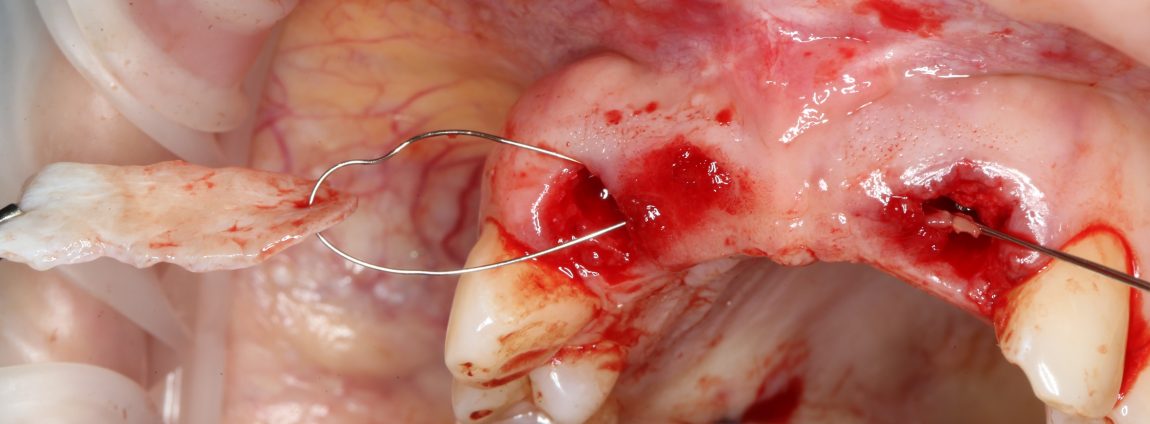

Следующий шаг — подготовка ложа под соединительнотканный аутотрансплантат или, проще говоря — под пересадку десны. Мы решили минимизировать травму, поэтому будем создавать подслизистый тоннель:

Это довольно просто, хотя и требуется известная аккуратность. Мы используем обычные инструменты для синуслифтинга:

Вы уже догадались, что мы не планируем дополнительных разрезов — весь объём работы мы проведём через лунки зубов. Таким образом, мы снизим травматичность нашей операции и, как следствие, риск возможных осложнений.

Создание тоннеля в области центральных резцов занимает 10-15 минут. В последующем, мы проведём и зафиксируем в нём соединительнотканный аутотрансплантат, который создаст необходимый для эстетики объём мягких тканей:

Теперь нам нужно провести и зафиксировать его в тоннеле между лунками удалённых зубов. Для проводки мы решили использовать ортодонтическую проволоку. Как показала практика, это очень удобно и легко.

Суть такова. Сначала мы проводим проволоку через тоннель:

Затем прокалываем ей аутотрансплантат и проводим конец со стороны нанизанного трансплантата обратно:

Таким образом, можно легко и малотравматично «протащить» аутотрансплантат любого размера в сформированный тоннель любой длины: